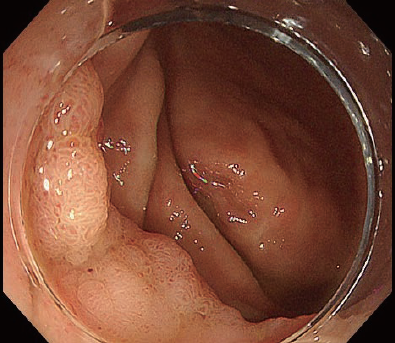

The first thing to do after introducing the DualKnife J into the submucosal layer is to excavate the blue submucosal layer in front of you toward the most distal position possible. Rather than immediately proceeding to circumferential incision, dig and advance in the central part immediately beneath the lesion. This is known as the pocket-creation method (PCM)¹. After widening the pocket to a certain extent, perform dissection with the goal of opening the pocket to both the left and right (Fig. 7).

What is important here is to advance dissection by making use of the DualKnife J’s precision. Your goal should be to remove fibers one by one along the optimal dissection line.

Fig. 7